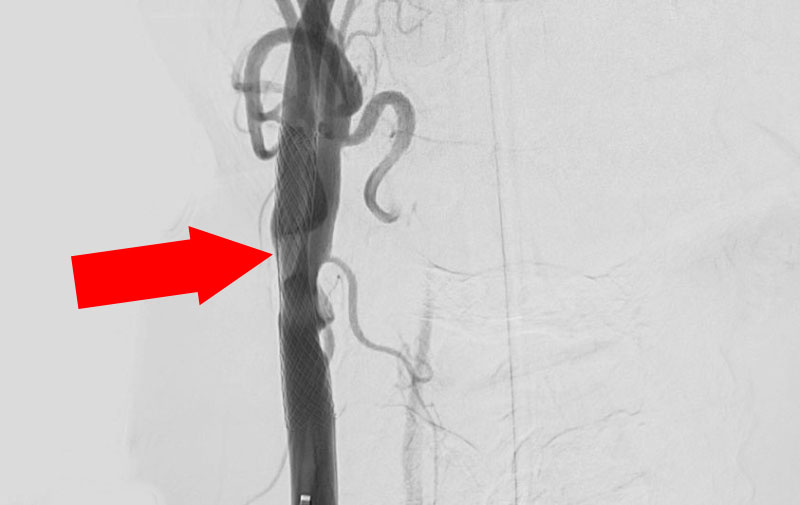

1244

'22年6月24日

左内頚動脈狭窄症

70代

院内外来